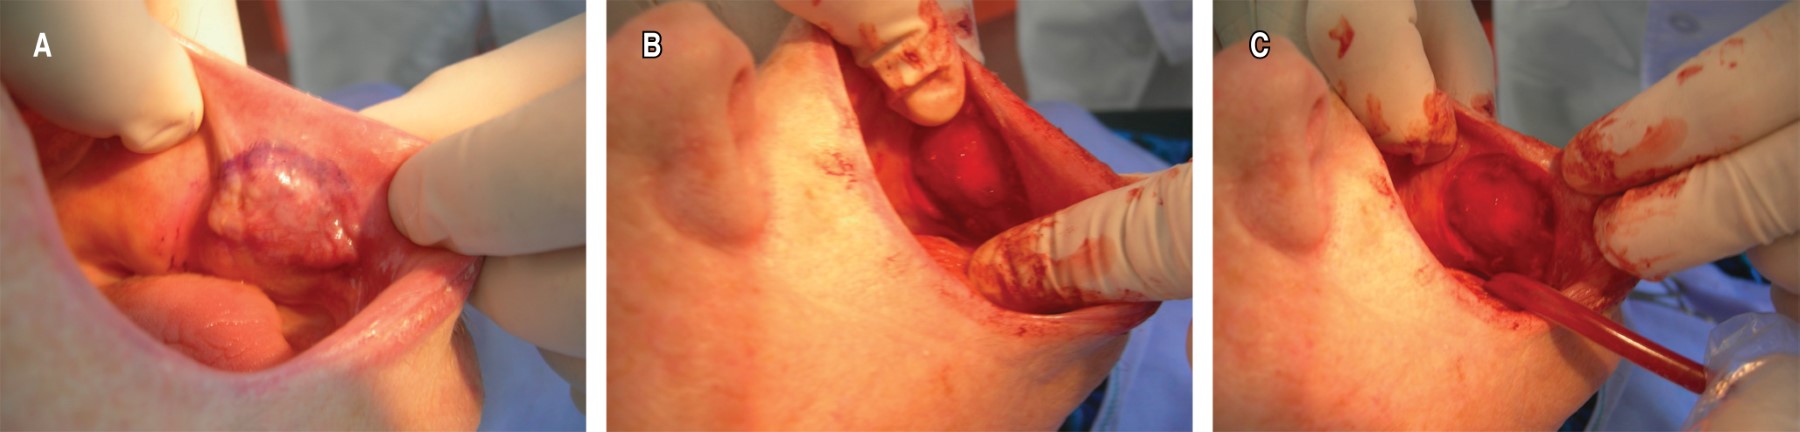

Basal cell adenocarcinoma of the minor salivary gland of the cheek

Salivary tumors can develop under the same histologic morphology in any of the glands. Of these, 80% occur in the parotid gland, 10 to 15% in the submaxillary gland and 5 to 10% in the sublingual and minor salivary glands. In major salivary gland tumors, approximately 80% are benign, but in minor salivary glands 35 to 80% are malignant, with clinical and histopathologic variations. The probability of a salivary tumor being malignant increases the smaller the size of the gland in which it is located. Minor salivary gland tumors (MSGTs) are rare, accounting for 10-15% of all salivary neoplasms. Despite their relatively low frequency, MSCTs constitute a heterogeneous group of neoplasms with a wide variety of histologic types.

Figure 2

Figure 3

Figure 4